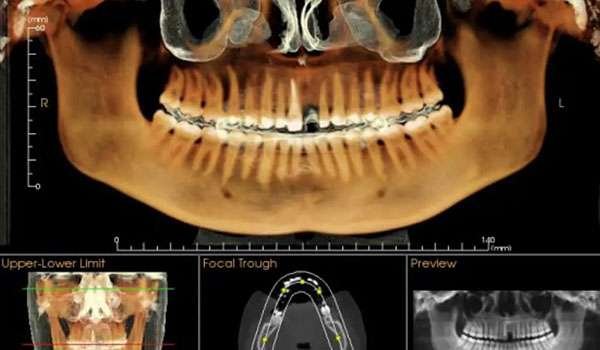

CBCT (Cone Beam Computed Tomography) is a specialized type of X-ray equipment used when regular dental or facial X-rays are not sufficient. It uses a cone-shaped X-ray beam to create detailed 3D images of the bone, soft tissues, nerve pathways, and dental structures in a single scan. This technology is particularly useful for evaluating complex cases and planning surgical procedures.

3. Image Processing: The captured images are compiled to create a comprehensive 3D representation of the scanned area. This detailed view allows our dentists to accurately assess your dental and bone structures.

• Detailed 3D Imaging: Provides a complete view of the bone, teeth, and soft tissues, enabling precise diagnosis and treatment planning.

• Improved Treatment Planning: Facilitates the planning of dental implants, orthodontic procedures, and other surgical treatments with high precision.